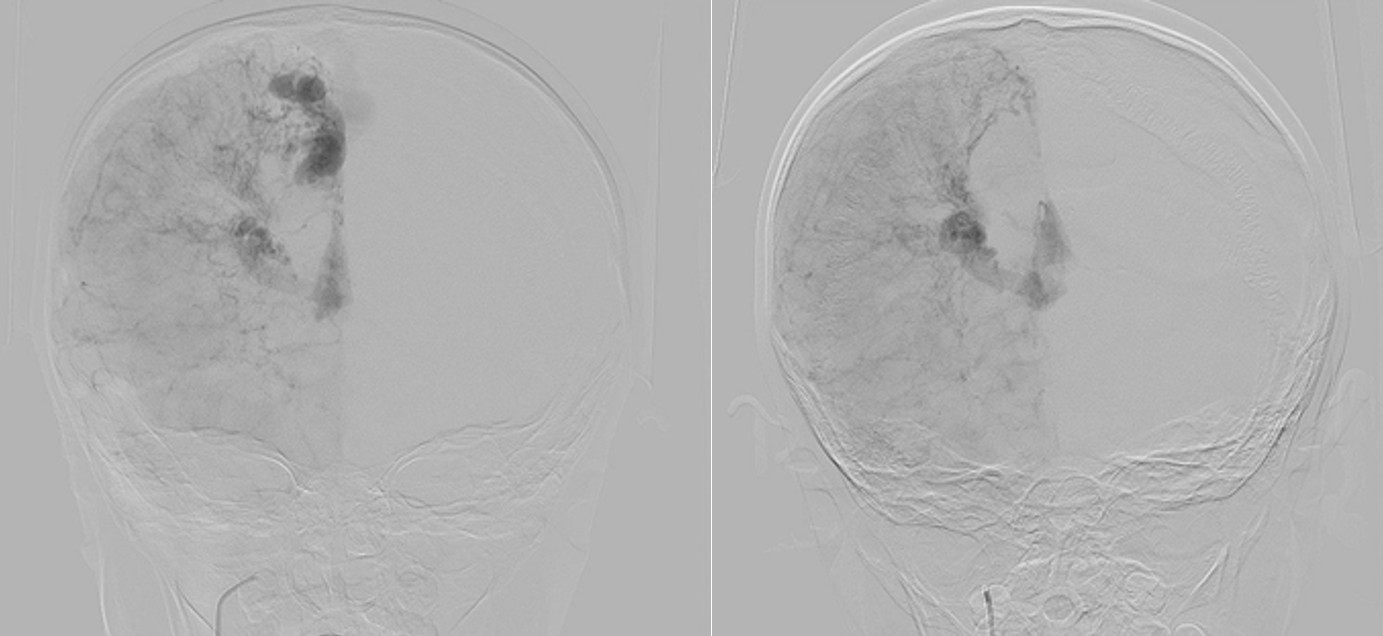

Digital subtraction angiography (DSA) confirmed the presence of two AVMs: one fed by distal branches of the right ACA and draining into the superior sagittal sinus, and another fed by MCA branches, draining into the internal cerebral vein. Capillary anastomoses were noted between the two AVMs. Selective bilateral internal carotid artery (ICA) injections revealed globally abnormal, tortuous arteriolar networks with delayed capillary filling, more pronounced on the right side (Figures 5, Figure 6, Figure 7). Based on these findings and the revised 2021 diagnostic criteria, the patient was diagnosed with MMD—characterized by stenosis of the intracranial ICA, narrowing at the terminal portion, and the development of abnormal collateral networks in the basal ganglia and periventricular white matter.4